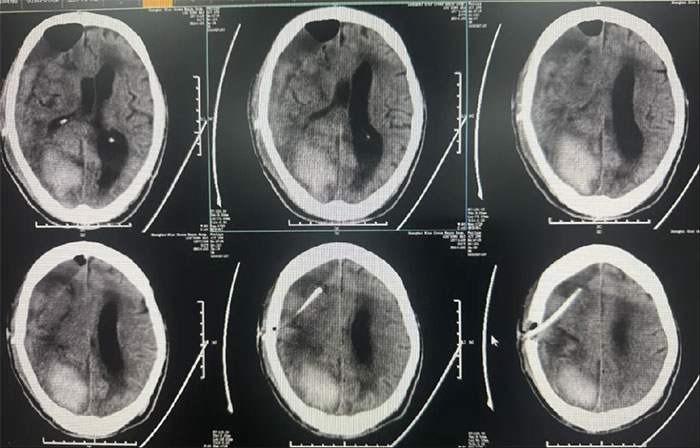

硬脑膜下钻孔引流术(长程引流管),引流管自右侧锁骨下皮肤穿出引流;

2025-02-18(发病后17天);

患者病情复杂,选择在局麻下进行,术程顺利。

● 长程引流硬膜下血肿;

术后中线偏移明显改善,颅内压降低,停用脱水药物;